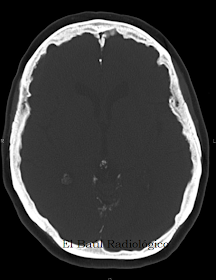

Mujer de 62 años que acude a su médico porque nota desde hace varios meses visión borrosa y cefalea persistente. No refiere antecentes clínicos de interés. A la exploración física el oftalmológo describe: proptosis bilateral y papiledema con pequeñas hemorragias y tortuosidad de las arcadas vasculares superiores de la papila. Ante los hallazgos descritos se solicita exploración de Tomografía Computarizada craneoencefálica para aclarar la causa del papiledema.

Mujer de 86 años que acude a urgencias porque nota desde hace varios meses cefalea persistente, disminución de la visión e inestabilidad. A la exploración física el oftalmológo descubre papiledema bilateral. Se solicita exploración de Tomografía Computarizada craneoencefálica para aclarar la causa del papiledema.